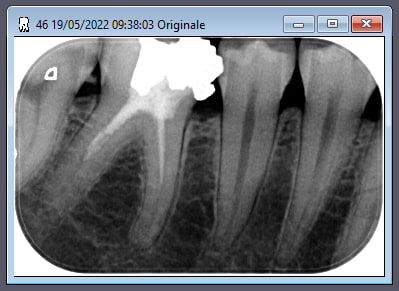

tiens la à l'instant par exemple celui qui a commis ca sur une jeune fille de 26 ans, il a son DPC nickel...

Pour rester dans le sujet, y a t il besoin d'une formation pour faire face a des cas comme le montre la radio de le mondeestvaste?

" Pour rester dans le sujet, y a t il besoin d'une formation pour faire face a des cas comme le montre la radio de le mondeestvaste? "